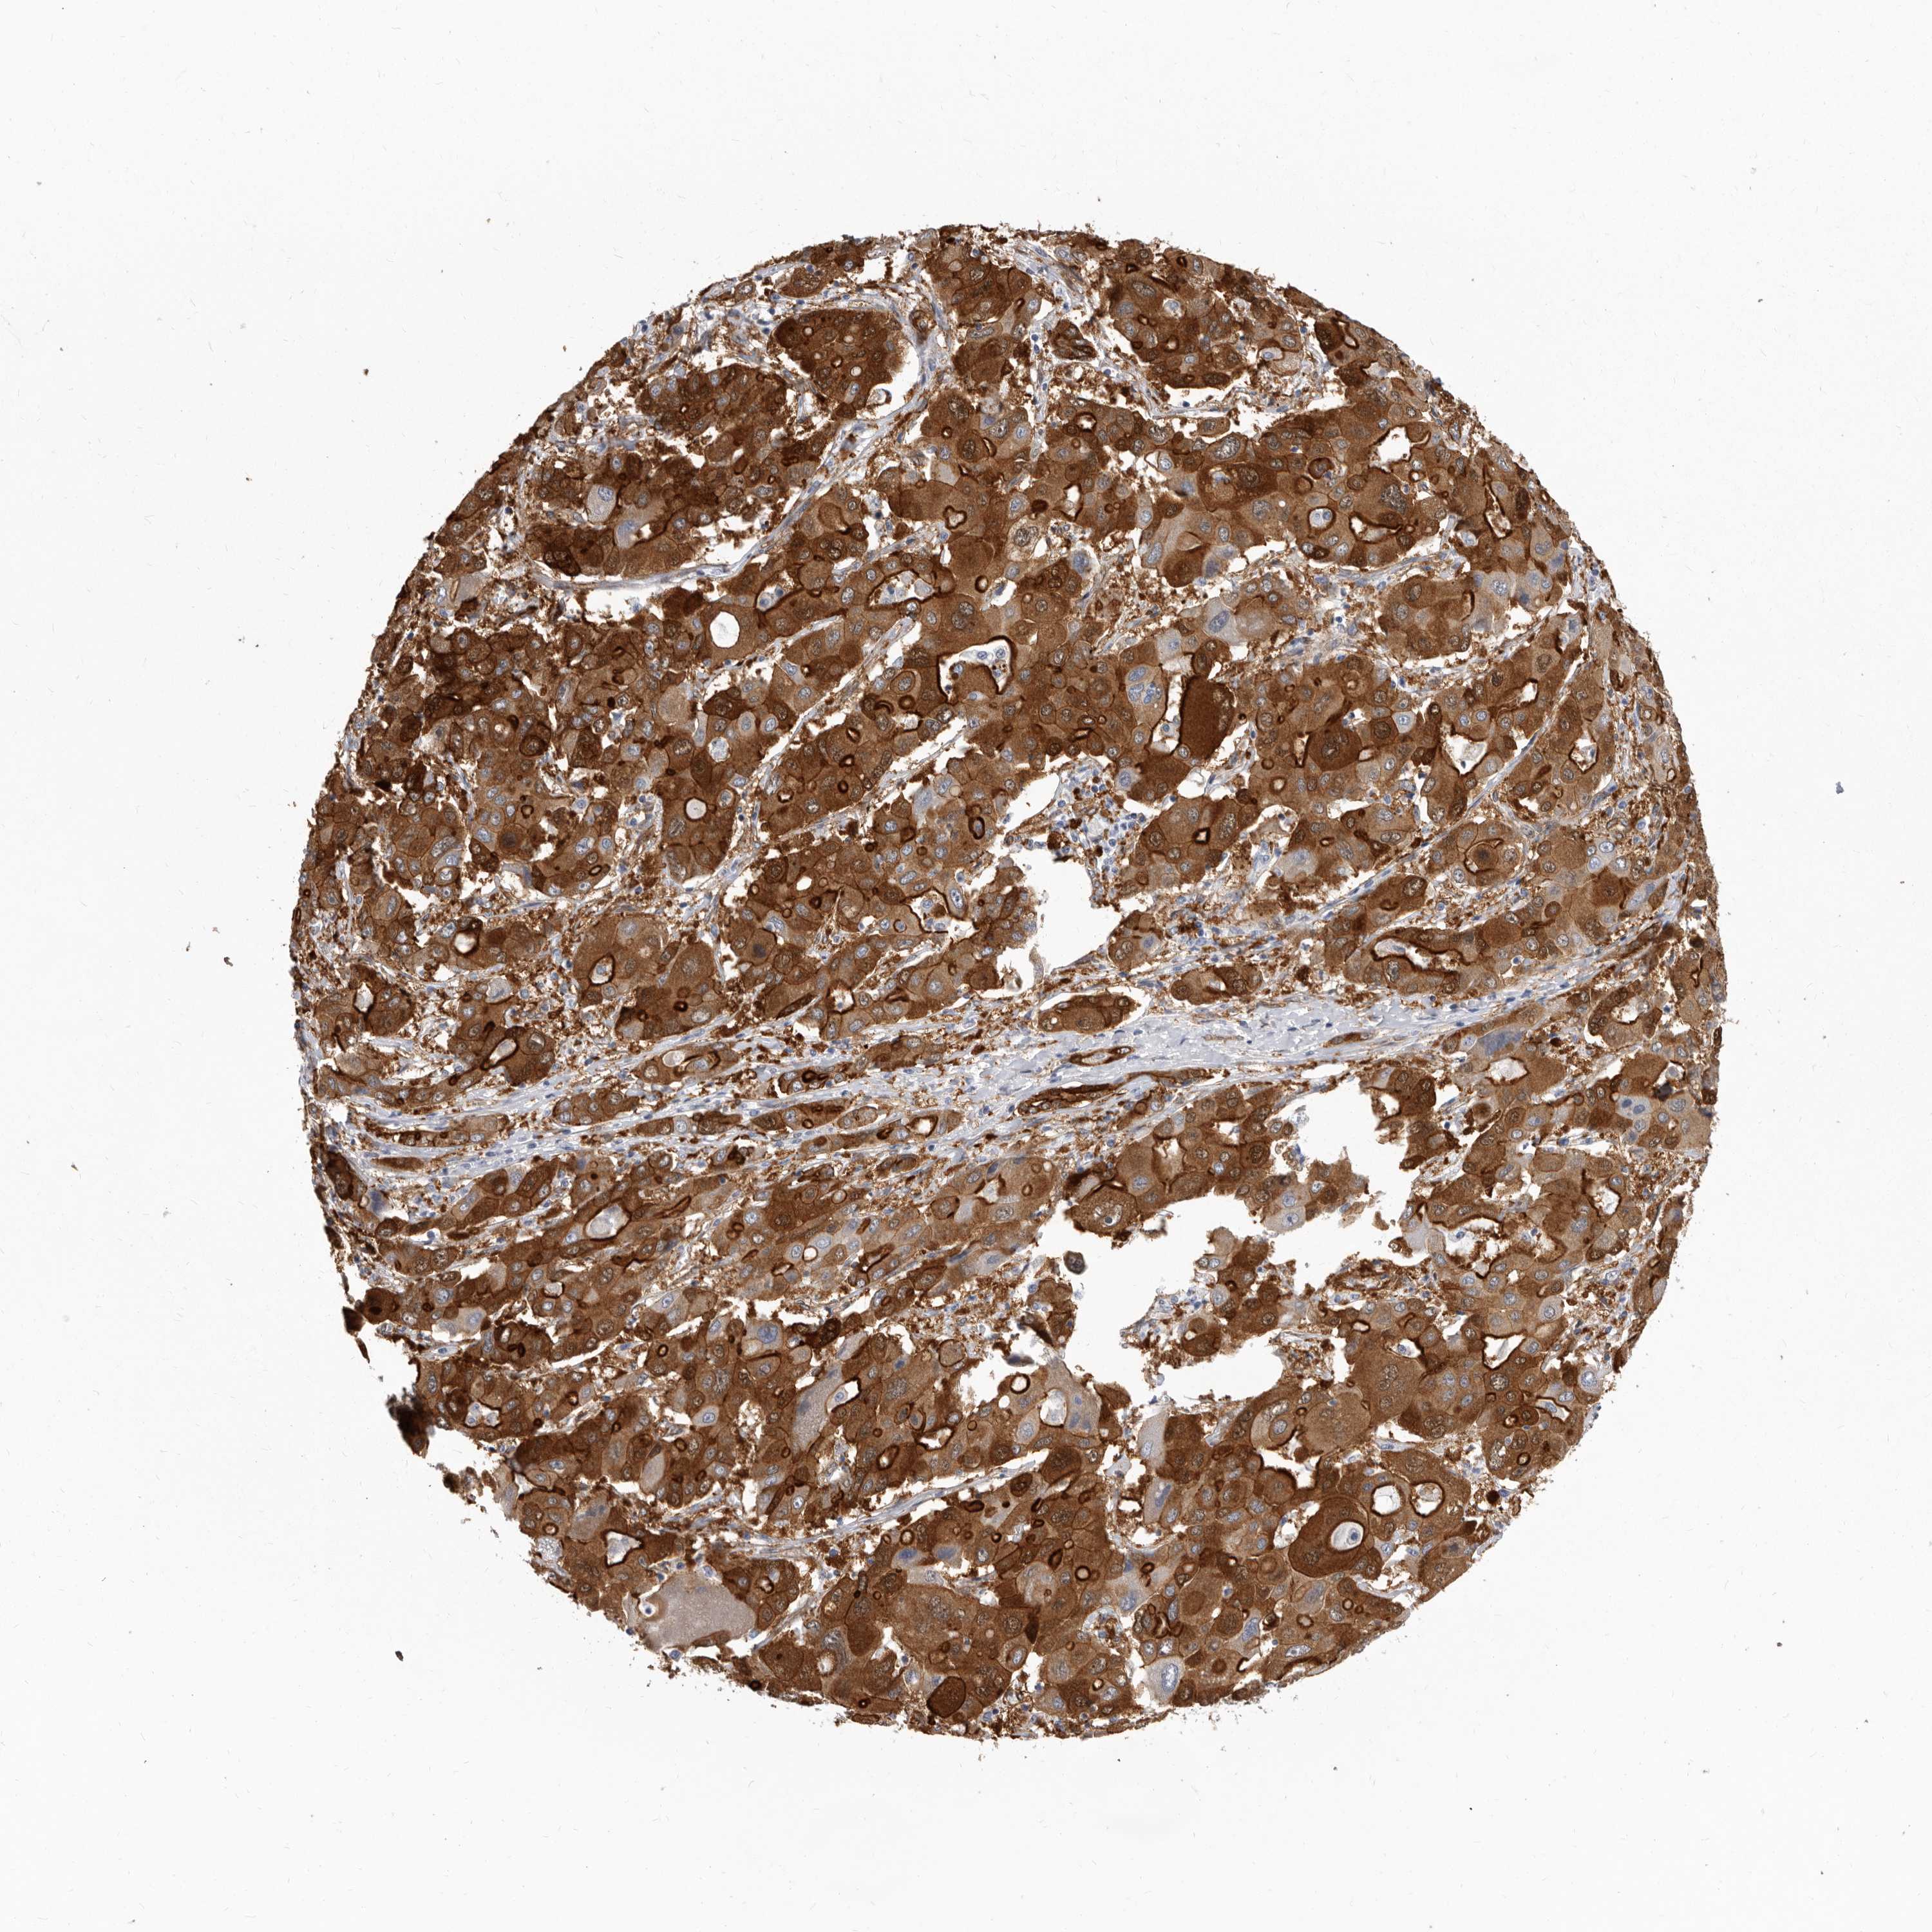

LIVER CANCER - Protein expressioni

A mouse-over function shows sample information and annotation data. Click on an image to view it in a full screen mode. Samples can be filtered based on level of antibody staining by selecting one or several of the following categories: high, medium, low and not detected. The assay and annotation is described here.

Antibody stainingi

Antibody staining in the annotated cell types in the current human tissue is reported as not detected, low, medium, or high, based on conventional immunohistochemistry profiling in selected tissues. This score is based on the combination of the staining intensity and fraction of stained cells.

Each image is clickable and will lead to virtual microscopy that enables deeper exploration of all samples and also displays staining intensity scores, fraction scores and subcellular localization as well as patient and tissue information for each sample.

Antibody HPA028448

Antibody HPA028696

Staining

High

Medium

Low

Not detected

Intensity

Strong

Moderate

Weak

Negative

Quantity

>75%

75%-25%

<25%

None

Location

Nuclear

Cytoplasmic/membranous

Cytoplasmic/membranous,nuclear

Cholangiocarcinoma

Carcinoma, Hepatocellular, NOS